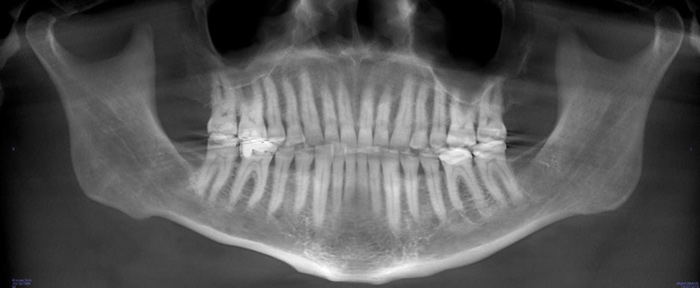

A comprehensive dental exam was performed that included a blood pressure test, an oral cancer screening, intraoral photographs, full mouth radiographs, a periodontal chart, a saliva test, and a CBCT scan. The exam confirmed the presence of active dental decay, periodontitis (ie, stage III, grade B), and areas of calcifications in his carotid artery (Figure 1 through Figure 3).

(1.) CBCT panoramic view.

Figure 1